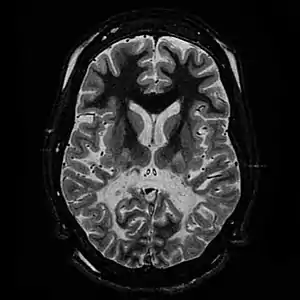

| T2 weighted axial scan at the level of the caudate heads demonstrates marked loss of posterior white matter, with reduced volume and increased signal intensity. The anterior white matter is spared. Features are consistent with X-linked adrenoleukodystrophy. | |

The degeneration of white matter, which shows the degeneration of myelin, can be seen in a basic MRI and used to diagnose leukodystrophies of all types. T-1 and T-2 weighted FLAIR images are the most useful. FLAIR stands for fluid-attenuated inversion recovery.[25] Electrophysiological and other kinds of laboratory testing can also be done. In particular, nerve conduction velocity is looked at to distinguish between leukodystrophy and other demyelinating diseases, as well as to distinguish between individual leukodystrophies. For example, individuals with X-ALD have normal conduction velocities, while those with Krabbe disease or metachromatic leukodystrophy have abnormalities in their conduction velocities.[25] Next generation multigene sequencing panels for undifferentiated leukodystrophy can now be offered for rapid molecular diagnosis after appropriate genetic counselling.